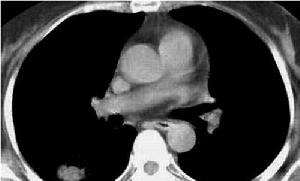

(1)肺間質纖維化胸部X 線檢查:可發現雙下肺網狀及結節狀密度增高陰影,病變嚴重時可累及雙側全肺,少數病例胸部平片可以正常。肺功能檢查可呈不同程度的限制性通氣功能障礙和彌散功能降低。肺組織病理檢查可見非典型Ⅱ型肺泡上皮細胞增生、肺泡炎或肺間質炎症以及不同程度的肺間質纖維化。

(2)閉塞性細支氣管炎伴機化性肺炎(BOOP)胸部X 線檢查可發現雙肺多發性斑片狀浸潤影。肺功能檢查即可呈限制性通氣功能障礙也可呈阻塞性通氣功能障礙。皮質激素治療反應良好。

(4)過敏性肺炎胸部X 線可見腺泡結節樣浸潤且病變多位於雙肺外周。肺功能檢測呈不同程度的限制性通氣功能障礙和低氧血症。肺活檢可見肺泡腔內有多形核白細胞或嗜酸性粒細胞及單核細胞浸潤。肺間質纖維化則較為少見。

(5)肺浸潤伴嗜酸性粒細胞增多胸部X 線片表現為斑片狀肺浸潤,常呈遊走性。

2、肺水腫 胸部X 線呈瀰漫性腺泡結節樣浸潤性改變而心臟大小形態正常。肺活檢可見肺水腫但很少有炎症反應。